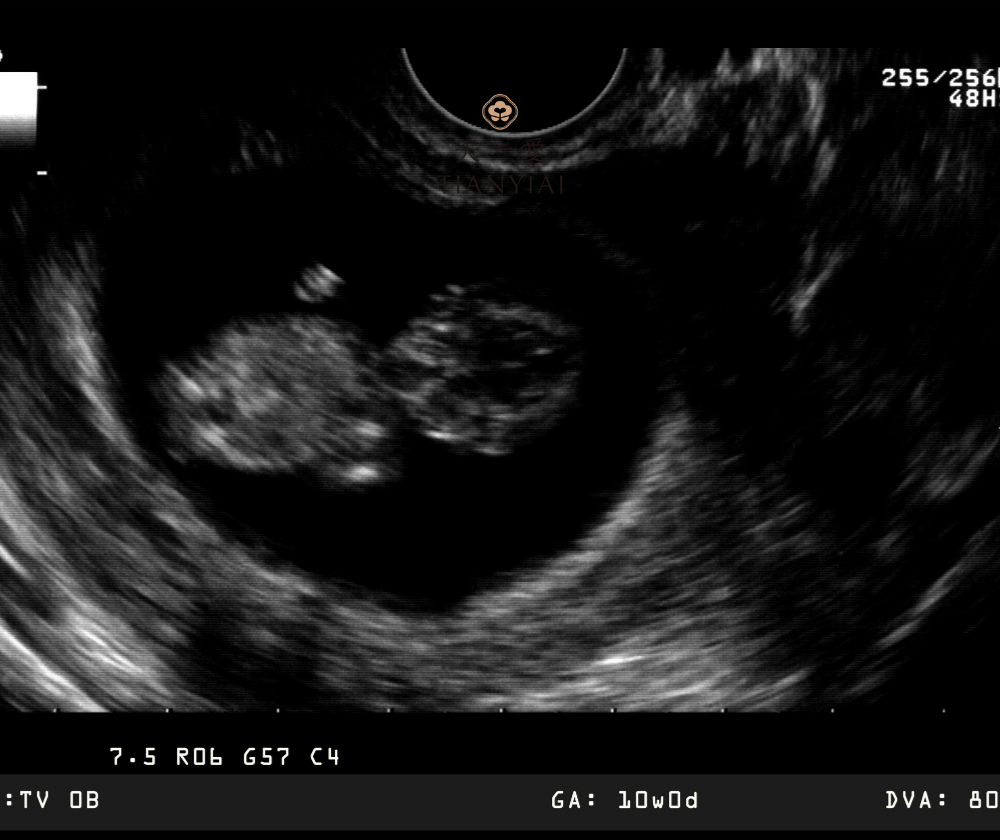

Các chuyên gia sản khoa khuyến nghị mẹ bầu có thể thực hiện xét nghiệm NIPT từ tuần thai thứ 10 trở đi, khi lượng ADN tự do của thai trong máu mẹ đủ để phân tích.

Xét nghiệm NIPT có thể làm từ tuần thai thứ 10